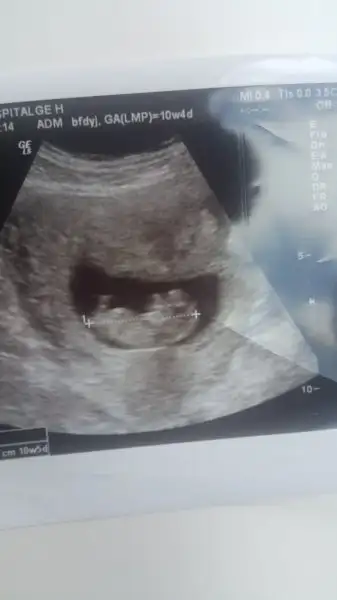

Doktor kontrolünden geldim ben de. Sağlık ocağına kayıt yaptırman gerekli artık dedi. %80 ihtimal kız ama alışveriş yapmayın değişebilir de dedi. Folik asiti bırakıp, D vitamin damlası ve megadyn pronatal vitamin verdi. Bunları doğuma kadar kullanacaksın dedi. Ultrasonda 12+4 çıktı. Kıpır kıpır hiç yerinde durmadı maşallah. Benden haberler bunlar kızlar

Gözün aydın canım ve ayrıca hayırlı olsun cinsiyet tahmininde bulunmuş doktor. Senin usg fotoğrafında çok erkek gibi gelmişti bana nub teorisine göre. Kesin değilmiş ama nub da yalan oldu şimdi benim gözümde

Ben de erkeğe benzetmiştim önceki ultrasonda canım. Gerçi alışveriş filan yapma kesin diyemiyorum dedi. Erkeklerin testisleri biraz geç iniyor aşağı, o yüzden yanıltabiliyor dedi. Önümüzdeki ay gideceğim kontrole bakalım o zaman netleşir herhalde